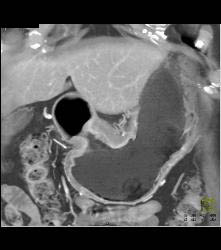

Antral Carcinoma